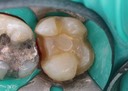

Joe Cha #18 prep